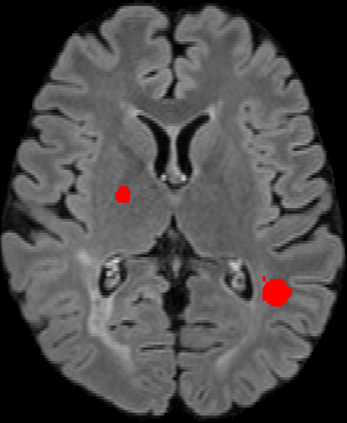

Assessment of lesions and their longitudinal progression from brain magnetic resonance (MR) images plays a crucial role in diagnosing and monitoring multiple sclerosis (MS). Machine learning models have demonstrated a great potential for automated MS lesion segmentation. Training such models typically requires large-scale high-quality datasets that are consistently annotated. However, MS imaging datasets are often small, segregated across multiple sites, with different formats (cross-sectional or longitudinal), and diverse annotation styles. This poses a significant challenge to train a unified MS lesion segmentation model. To tackle this challenge, we present SegHeD, a novel multi-dataset multi-task segmentation model that can incorporate heterogeneous data as input and perform all-lesion, new-lesion, as well as vanishing-lesion segmentation. Furthermore, we account for domain knowledge about MS lesions, incorporating longitudinal, spatial, and volumetric constraints into the segmentation model. SegHeD is assessed on five MS datasets and achieves a high performance in all, new, and vanishing-lesion segmentation, outperforming several state-of-the-art methods in this field.